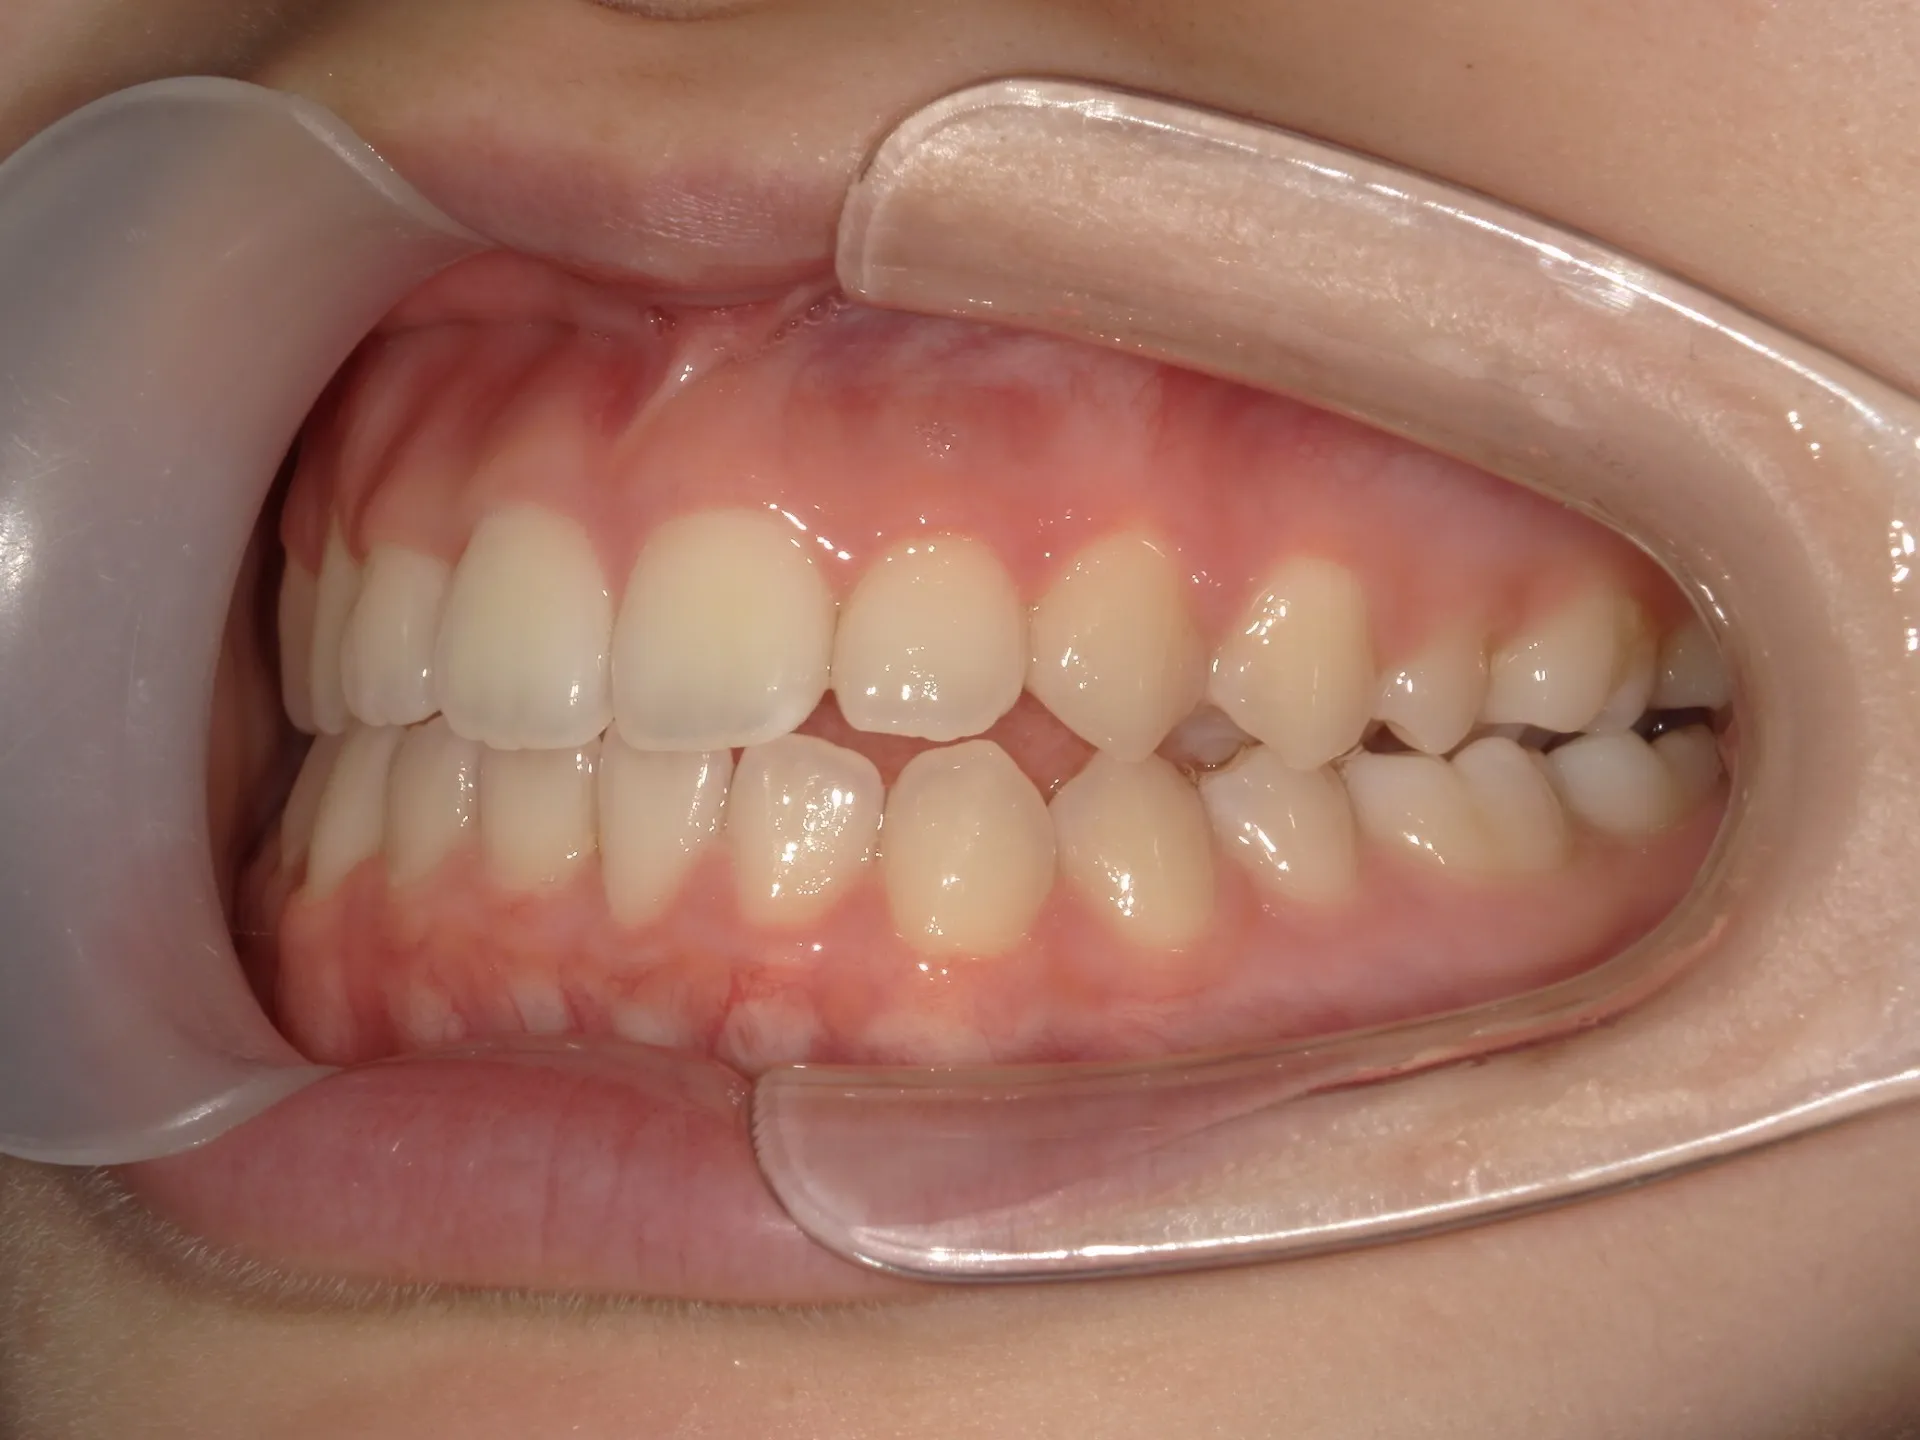

開咬治療前

正面観

まず開咬とは、文字通り開いている咬み合わせのことをさします。

分かりにくい方もいるかもしれませんのでもう少し説明すると、今回お見せしている写真では前歯部開咬と呼ばれる開咬です。

臼歯(奥歯)は噛んでいるのに前歯が咬みあわないで開いているという状態のことを前歯部開咬と言います。

さて、治療前の正面観は先ほど述べた通り、前歯部開咬で奥にある舌が見えているのが分かります。